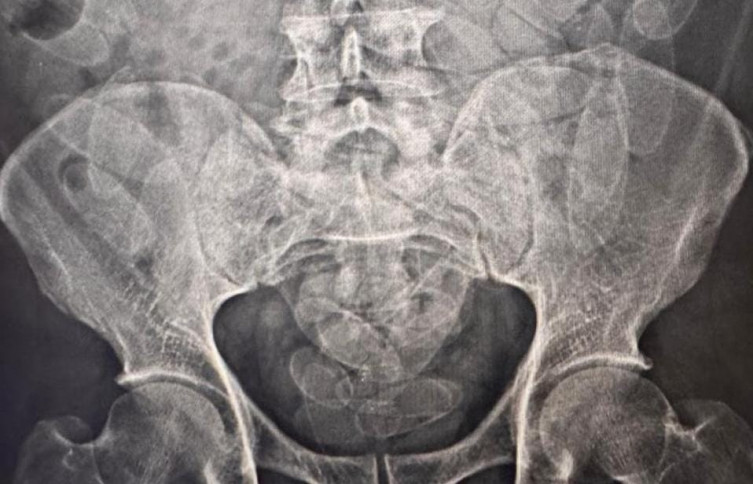

Exame de raio-x comprovou a ingestão de cápsulas de droga pelos detidos

Foram identificados indícios de que os passageiros poderiam ter engolido cápsulas de droga. Os três foram levados para a Santa Casa de Corumbá, onde exames de raio-x comprovaram a suspeita. Após expelirem todas as cápsulas, os presos serão encaminhados à Polícia Federal para prosseguimento das investigações.